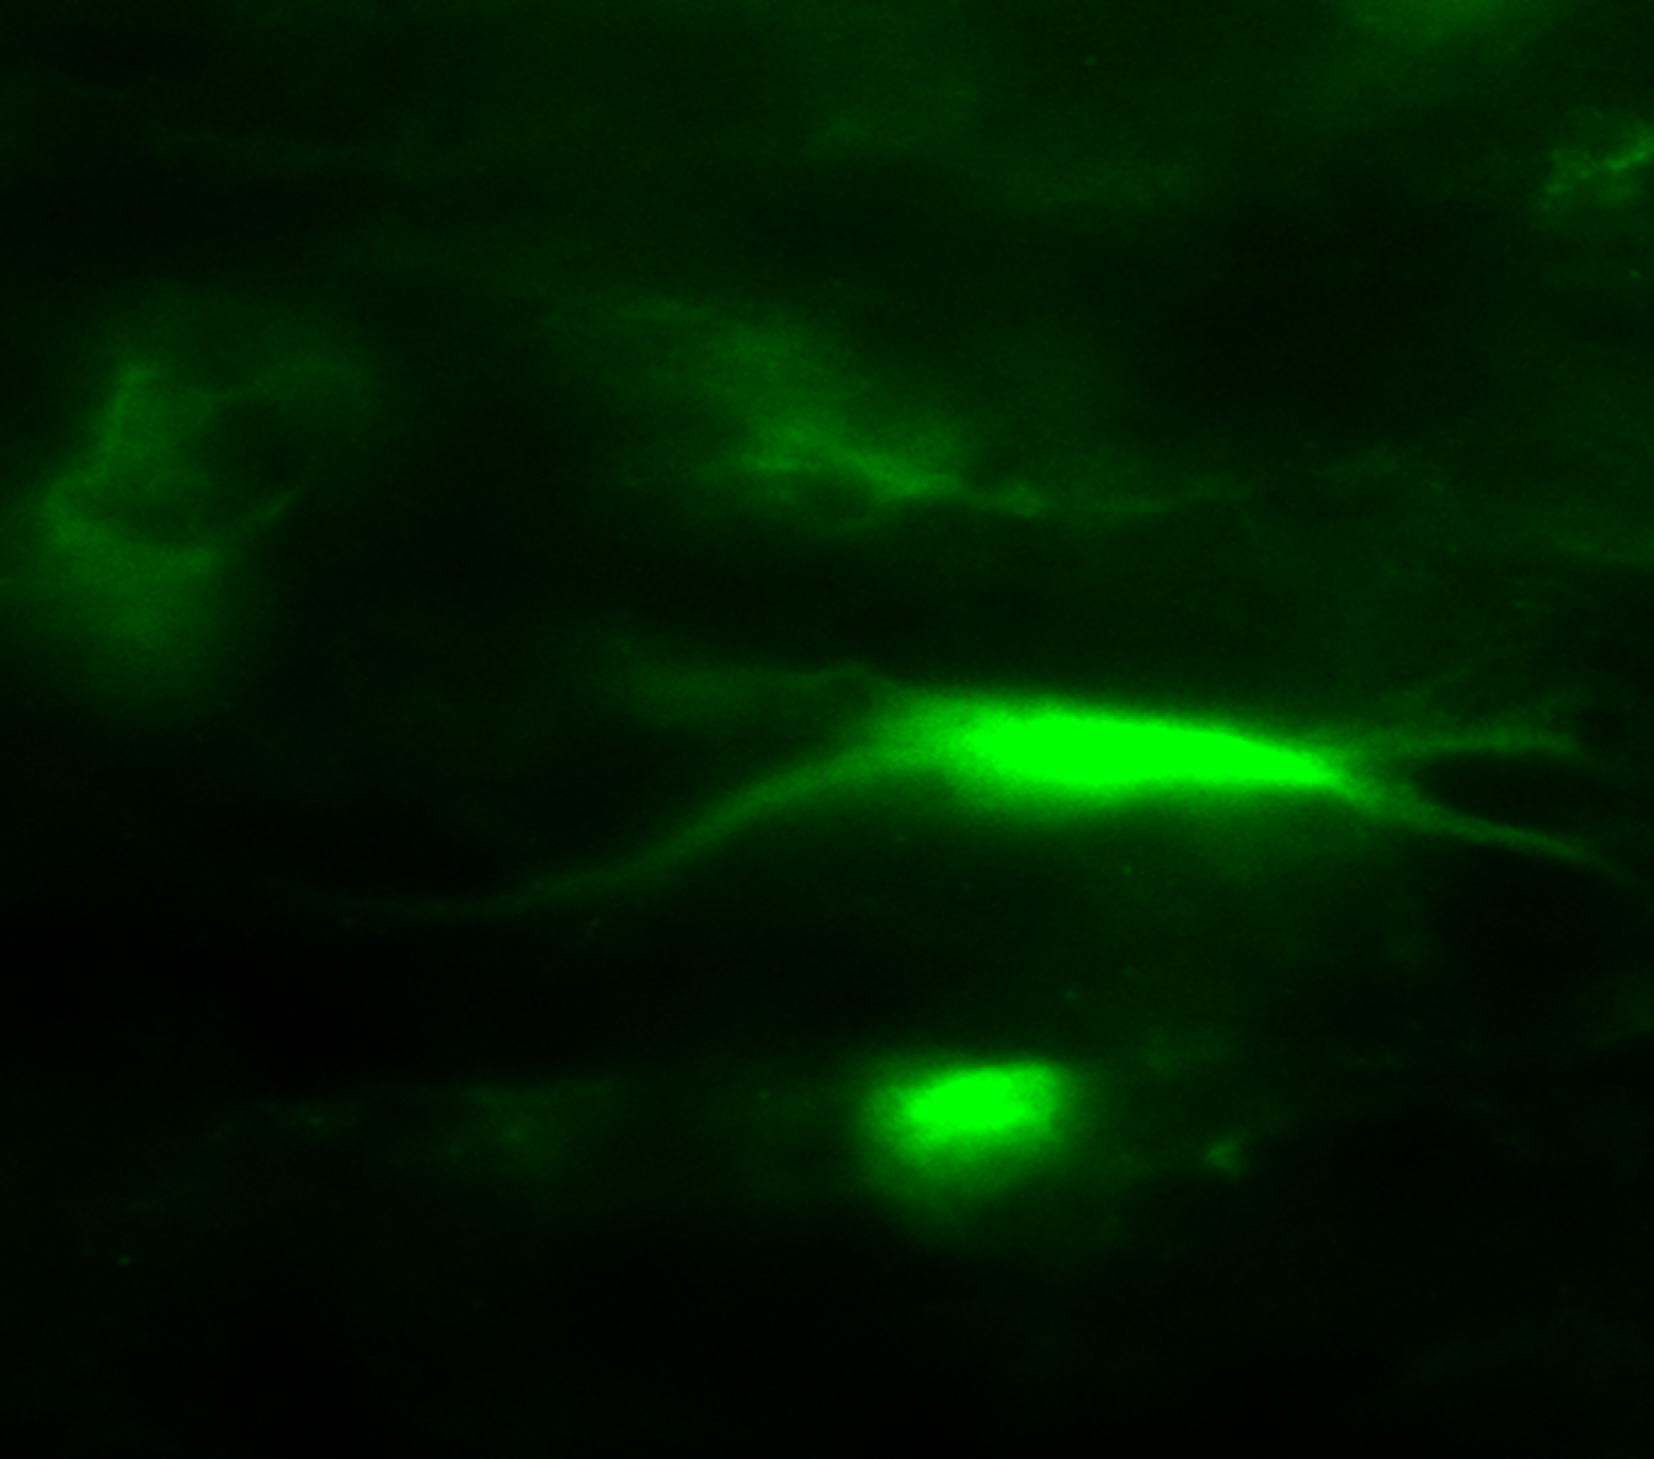

A mouse neuron expresses green fluorescent protein gene delivered by the nanoparticles developed at UB.

In the UB experiments, targeted dopamine neurons -- which degenerate in Parkinson's disease, for example -- took up and expressed a fluorescent marker gene, demonstrating the ability of nanoparticle technology to deliver effectively genes to specific types of cells in the brain.